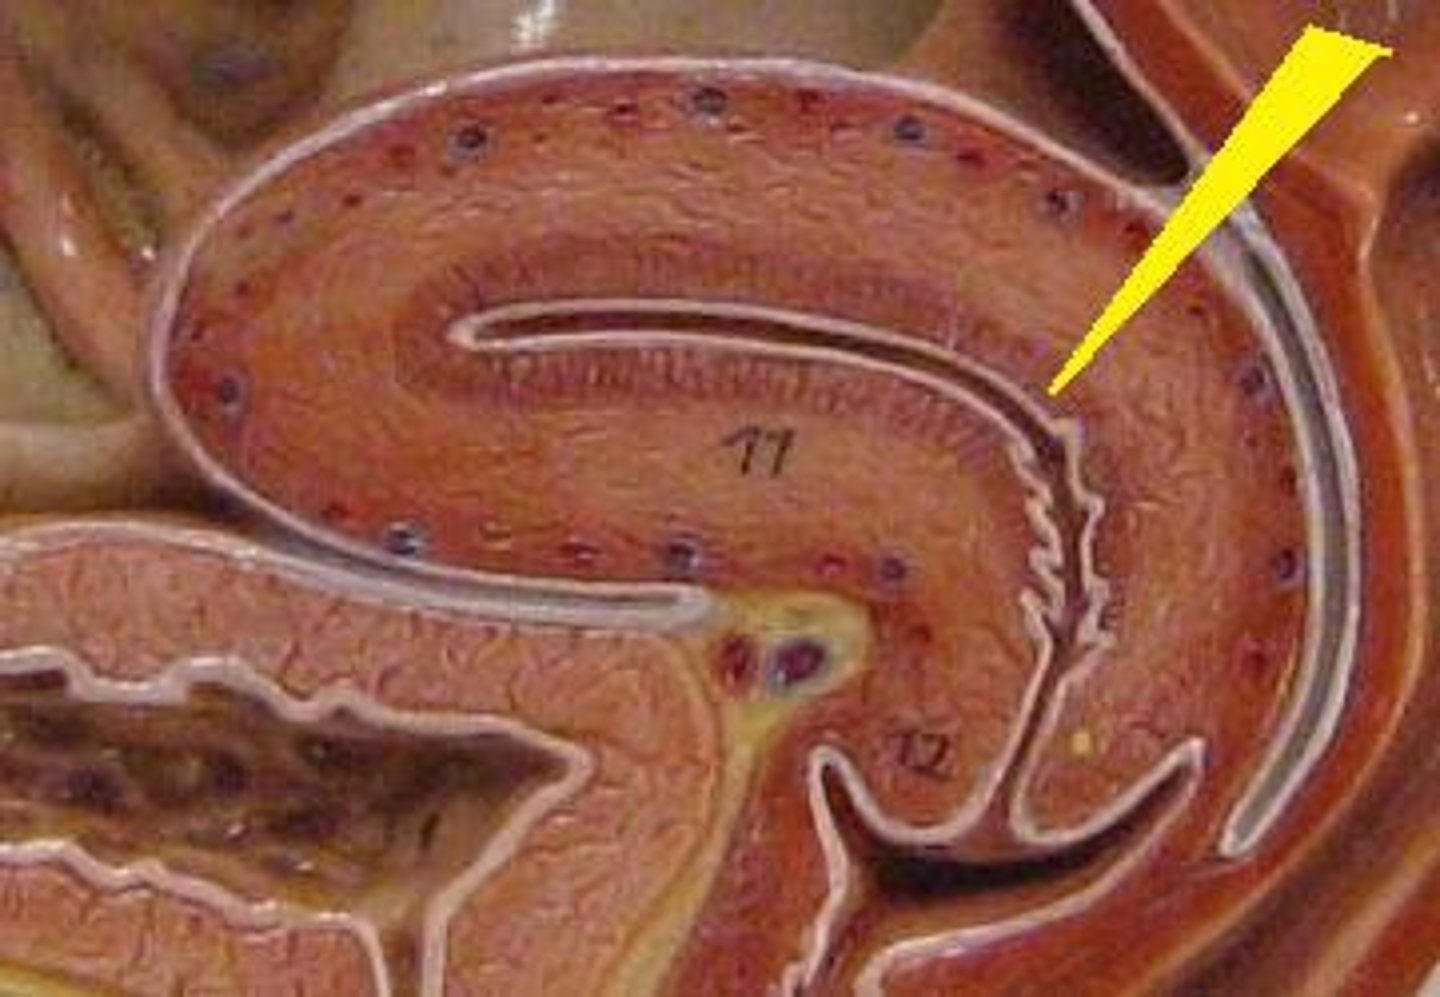

Primordial follicle

1

Primordial follicle

Primordial follicle

1

Primary follicle

2

Primary follicle

Primary follicle

2

Secondary follicle

3

Secondary follicle

Secondary follicle

3

Tertiary follicle

4

Tertiary follicle

4

Mature follicle

5

Mature follicle

Mature follicle

7

Antrum

10

Zona pellucida

9

Theca folliculi

8

Corona radiata

Corpus luteum

Corpus luteum

Corpus albicans

Corpus albicans

corpus luteum

8

early corpus luteum

9

late corpus luteum

10

corpus albicans

11

granulosa cells

12

theca cells

13

antrum

14

ovary

1

primordial follicle

a

secondary follicle

b

ruptured follicle

c

granulosa cells

d

corpus luteum

e

secondary oocyte

g

ovum

h

zygote

i

blastocyst

l

endometrium

m

corpus albicans

f

uterus

3

fallopian tube

2